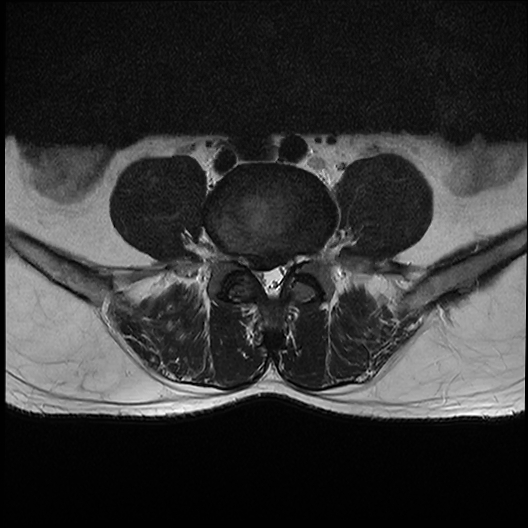

MRI提示L4/5椎间盘右侧突出明显

严重压迫神经根